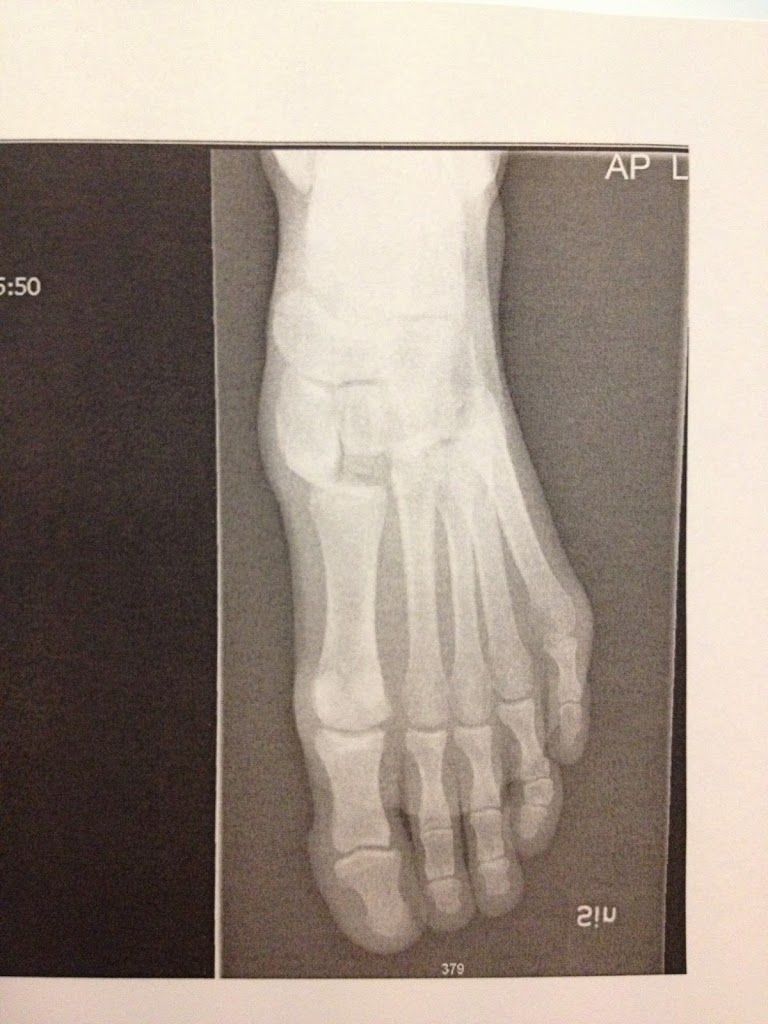

Alle de lange mellemfodsknogler (metatareser)

rykket til venstre (på billedet til højre) og

kilebenene (3 cunieforms) oppe over havde

også fået en tur plus lidt småfrakturer

Alle fodens knogler i mellemfoden var slået af led og nogle steder lidt frakturer. Metatarserne var nærmest rykket en hel plads til venstre og knoglerne oppe over stod heller ikke helt så fint på række længere.